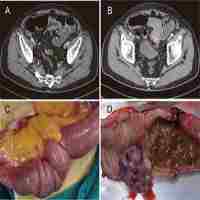

| Abstract | Background: Patients with renal cell carcinoma are often troubled by metastases, but masseter muscle metastases are particularly rare. Case Presentation: We reported a 76-year-old male who did not show any recurrence and metastasis after the nephrectomy until 5 years later. The metastatic mass was found with the protrusion of masseter muscle area. Computed tomography and ultrasonography indicated a hypervascular mass, and pathology confirmed the masseter muscle metastasis of renal cell carcinoma. Complete metastasectomy was performed with the preserval of facial function and appearance. No local recurrence or distant metastasis was found in follow-up. Conclusion: Our report indicates masseter muscle can be a metastatic site of renal cell carcinoma, regardless of its rarity. Long-term comprehensive surveillance is needed for patients with renal cell carcinoma. Muscle metastases can disguise as benign mass, multiple imaging and pathology are important in identifying their sources. If possible, complete metastasectomy with function retention is recommended for masseter muscle metastases. |